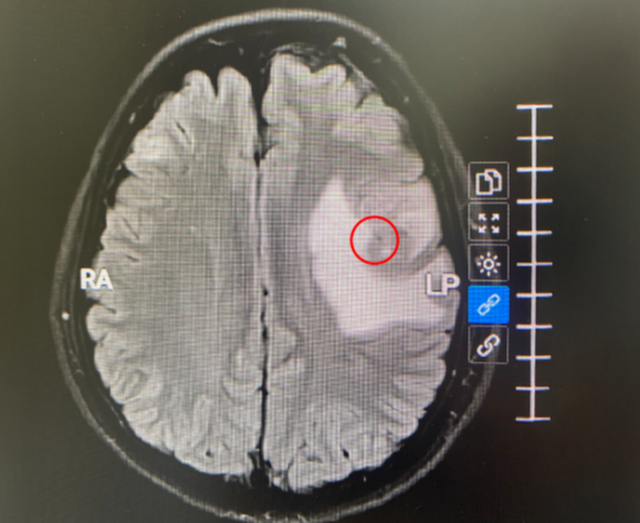

Khối u di căn não (khoanh tròn đỏ) gây phù nề vùng não xung quanh. Ảnh: BVCC

ThS.BS Ngô Tuấn Phúc, khoa Ung bướu, BVĐK Tâm Anh TP.HCM cho biết, u di căn ở não phát triển nhanh, gây phù não xung quanh, choán chỗ rải rác ở hai bán cầu và tiểu não, chèn ép não thất bên trái khiến chị nói khó, phù tay trái, khó thở.